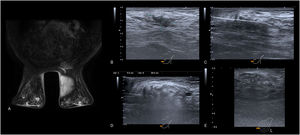

Figura 3.A y B) Mamografía con contraste en proyección mediolateral oblicua. Nódulo denso de morfología redondeada y contorno circunscrito en el cuadrante superoexterno de la mama izquierda, que asocia microcalcificaciones pleomórficas finas que se extienden más allá del límite de la lesión. En las imágenes recombinadas, tanto el nódulo como el área de microcalcificaciones presentan realce intenso y heterogéneo. Tras la realización de BAG, se obtuvo un resultado de carcinoma ductal infiltrante Triple Negativo. C-F) Imágenes de la ablación guiada por ecografía. C) Planificación del abordaje de la lesión, con marcador metálico en su interior. El nódulo se encuentra a unos 3 mm del plano cutáneo. D) Dada la cercanía de la lesión de la piel, se realiza hidrodisección con suero fisiológico para separar los planos. E y F) Posteriormente se comienza la ablación, evidenciándose los cambios durante el tratamiento, si bien no se consiguió una ablación completa. G) Imagen ecográfica del control realizado al mes de la intervención, donde se observan cambios postratamiento en evolución, con cierta degeneración quística interna y necrosis grasa a su alrededor. H) Mamografía con contraste en proyección mediolateral oblicua realizada a los 6 meses del procedimiento. En la zona donde previamente se encontraba la lesión ablacionada se observa un área de realce nodular de menor tamaño comparado con el nódulo inicial, que asocia otros realces lineales periféricos. Estos hallazgos son compatibles con resto tumoral/recidiva.

A y B) Mamografía con contraste en proyección mediolateral oblicua. Nódulo irregular de bordes espiculados de 26 mm localizado en cuadrante superoexterno de la mama izquierda, que condiciona retracción cutánea. En las imágenes recombinadas se observa un realce intenso de la lesión. Tras la realización de BAG, se obtuvo un resultado de carcinoma ductal infiltrante Luminal B. C-E) Imágenes de la ablación guiada por ecografía. C) Tras la planificación del abordaje, y debido al tamaño y cercanía del nódulo con el plano cutáneo, se decidió realizar la ablación realizando 2 pases. D) En primer lugar se realizó la ablación de la parte más irregular y profunda E) para posteriormente ablacionar la parte central y superficial, D y E) realizándose durante todo el procedimiento hidrodisección continua del plano subcutáneo y aplicación de hielo local para evitar el calentamiento de la piel (D y E). F) Imagen ecográfica del control realizado al mes de la intervención. Se observan cambios postratamiento con cierta degeneración quística interna y necrosis grasa a su alrededor.

En nuestra serie, hemos objetivado restos tumorales/signos de recidiva local en un caso, concretamente en una lesión con resultado anatomopatológico de carcinoma ductal infiltrante Triple Negativo con índice de proliferación Ki del 40%, que presentaba un tamaño en el momento del diagnóstico de unos 31 mm, cercano a la piel (fig. 3). La detección de la misma se evidenció en el control realizado con ecografía y mamografía con contraste a los 6 meses de la ablación, donde se observó el desarrollo de un área de realce nodular donde previamente se localizaba la lesión y unos realces periféricos lineales de nueva aparición. Estos hallazgos se confirmaron con la realización de una BAG guiada por ecografía.

Hasta el momento, en nuestra serie de pacientes solo hemos evidenciado un caso de persistencia tumoral/recidiva a los 6 meses de la ablación. Se trataba de un nódulo con tamaño en el límite alto y muy cercano piel (a menos de 5 mm), lo que impidió realizar ablación con margen de tejido sano. Además, presentaba criterios histológicos de mal pronóstico (Triple Negativo con alto índice proliferativo). Por ello, reincidimos en la importancia de realizar una selección adecuada de los pacientes con el fin de asegurar una ablación completa.

En los casos en que la lesión se encuentre cercana a la piel, músculo pectoral o aréola, se realizará hidrodisección utilizando una aguja espinal y suero fisiológico a baja temperatura, para evitar que dichas estructuras alcancen altas temperaturas. Además, es útil aplicar compresas frías en tumores próximos al plano cutáneo (fig. 3).